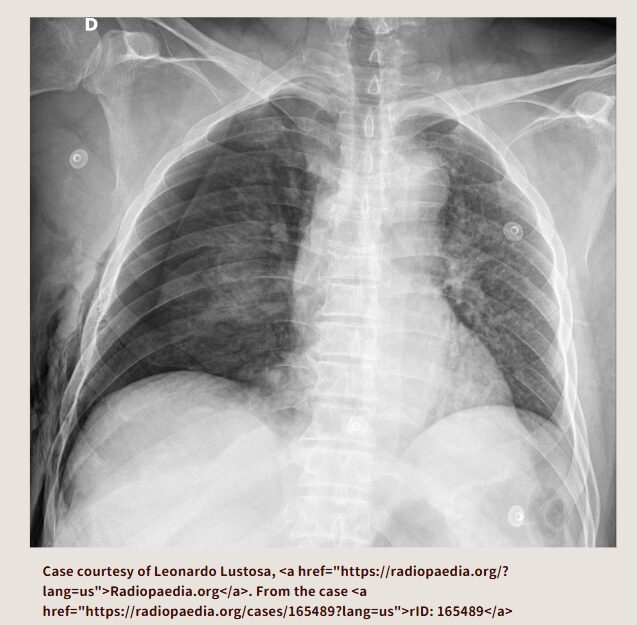

この胸部レントゲン画像はどうでしょうか? ぱっと見て思うのは、おそらくモニター心電図の電極が付いていて、左の肺が白ぽいので肺炎かな、状態悪そうだなということです。気胸はどこにあるでしょうか?

右肺が気胸になっています。

この胸部レントゲンはどうでしょうか? 左の肺の外側が黒っぽいですよね。

左の気胸になっています。

アスピレーションチューブを左胸腔に留置して、脱気しています。それで左肺が膨らんでいます。